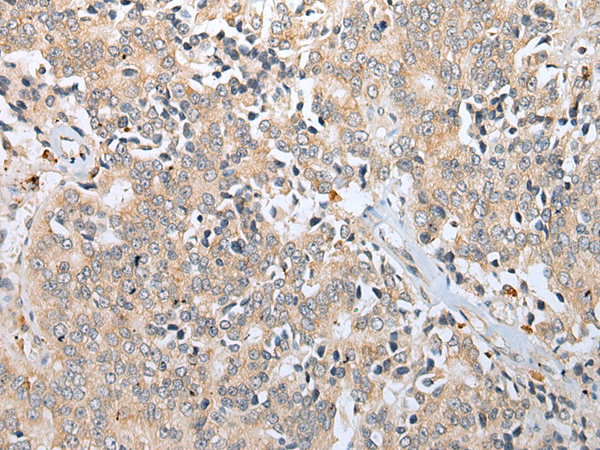

分类: 科研抗体货号: P09112别名: CFM2; FAM101A应用: IHC反应种属: Human